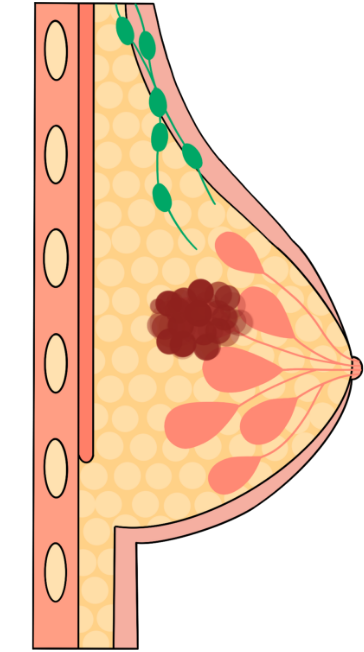

Breast cancer happens when the cells in the breast change and grow out of control. Breast cancer affects 1 in 8 women in the U.S. and is the most common cancer in women.

Breast cancer is classified based on the type of cells where the cancer forms and whether it spreads.

- Invasive breast cancer – cancer cells have spread beyond the place where they first formed and can invade other parts of the body.

- Non-invasive breast cancer (in-situ)– abnormal cancer cells stay in the tissue where they formed and have not spread.

One of the most used tests is a screening mammogram. A mammogram is a low-dose x-ray. The x-ray picture shows your breast tissue including any abnormal areas. Mammograms cannot show if an abnormal area is cancer, but they can help your healthcare provider decide if you need more tests. You can only get a screening mammogram before you have symptoms. Once you have any symptoms you will need a diagnostic test.